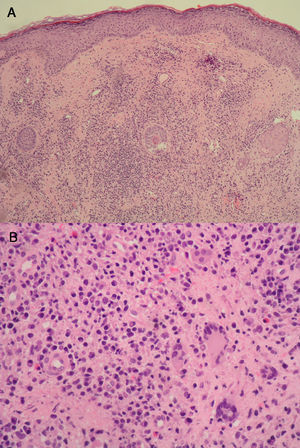

El estudio histológico puso de manifiesto la presencia de un infiltrado inflamatorio difuso en la dermis compuesto predominantemente por células plasmáticas, linfocitos y ocasionales células gigantes multinucleadas (fig. 3). No existía afectación epidérmica ni tampoco se observaron granulomas bien constituidos. La celularidad linfoide no mostraba atipia y las técnicas de inmunohistoquímica descartaron la posible recidiva de una neoplasia linfoide. La biopsia, con la eliminación del alambre y sutura directa, supuso la resolución del cuadro.